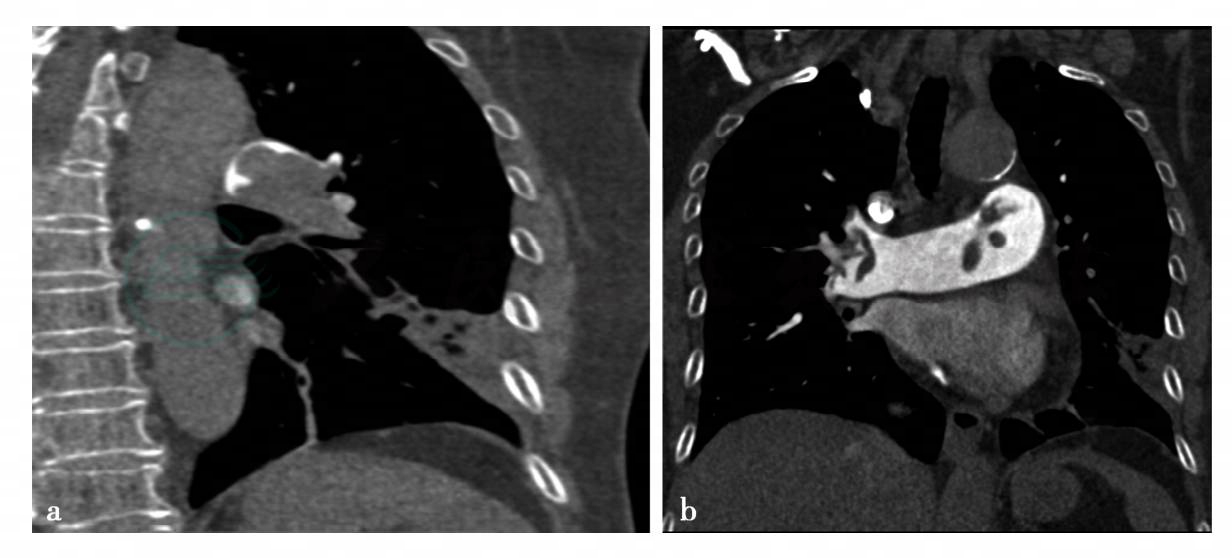

(1)病例4:

心脏与肺CT矢状位与冠状位重建。

图1 图1a~b,左、右肺动脉干及分支内多发低密度充盈缺损。

(1)病例4,急性肺栓塞。